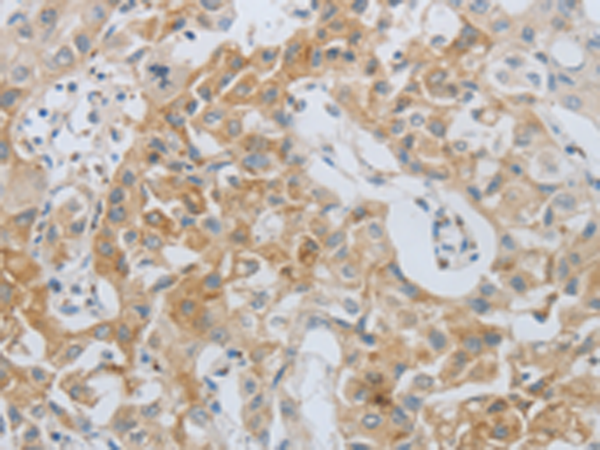

分类: 科研抗体货号: P11046别名: FRAP, FRAP1, FRAP2, RAFT1, RAPT1应用: IHC反应种属: Human, Mouse, Rat